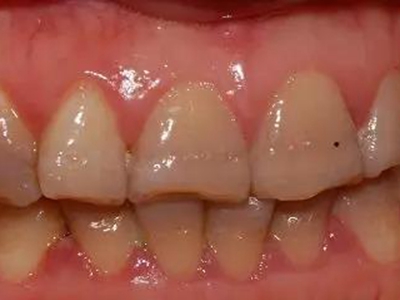

牙釉质发育不全牙齿变薄图

牙釉质发育不全患者的牙齿有色泽和透明度改变,表面出现白垩色釉质,同时牙齿顶端变透明、变薄,但患者可能无敏感、疼痛等自觉症状。